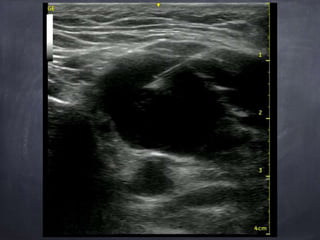

Ultrassom

Custo x Benefício

Sólido x Líquido

Pús

Anatomia

Ultrassonográfica

Características

Ultrassonográficas

Tamanho

referência : menor eixo

Níveis IB e II =8mm , IA, III, IV e V = 5mm

limite da detecção de metástases 3mm - para

qualquer método